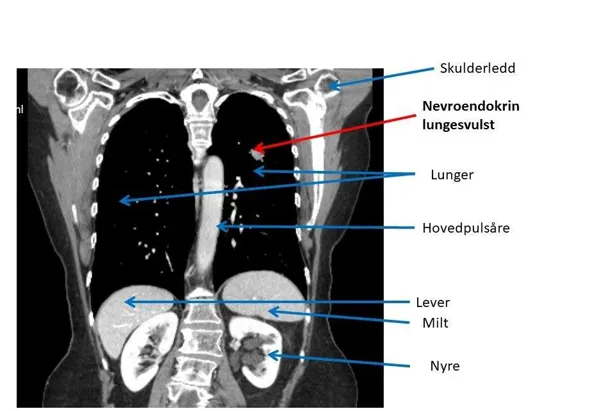

Røntgenundersøkelser

Ved hjelp av disse undersøkelsene kan en svulst påvises. Noen ganger kan imidlertid svulstene være såpass små, eller ligge slik til, at de ikke identifiseres på røntgenundersøkelsene. Ofte må det brukes kontrast på CT undersøkelsene for at svulsten skal oppdages (intravenøs kontrast i arteriell og portovenøs fase).

Likeledes vil MR-oppdage flere svulster og gi bedre tolkningsmuligheter av sykelige forandringer ved bruk av kontrast. MR er bedre til å påvise svulster i skjelettet enn CT.